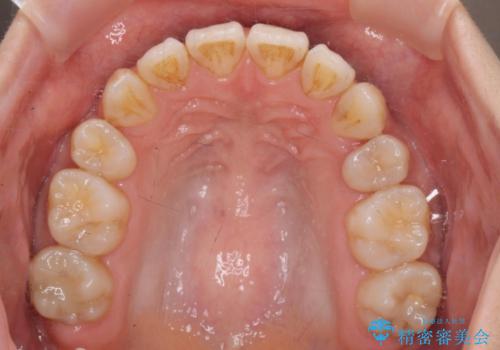

- 八重歯・がたつきのある歯並びの改善を求めて来院されました。

全部の歯が入り切るスペースがなかったため、小臼歯4本を抜去しワイヤーを用いたマルチブラケット矯正を選択しました。

歯並びの改善と共に、歯ブラシがしやすくなった!と喜んでいただくことができました。